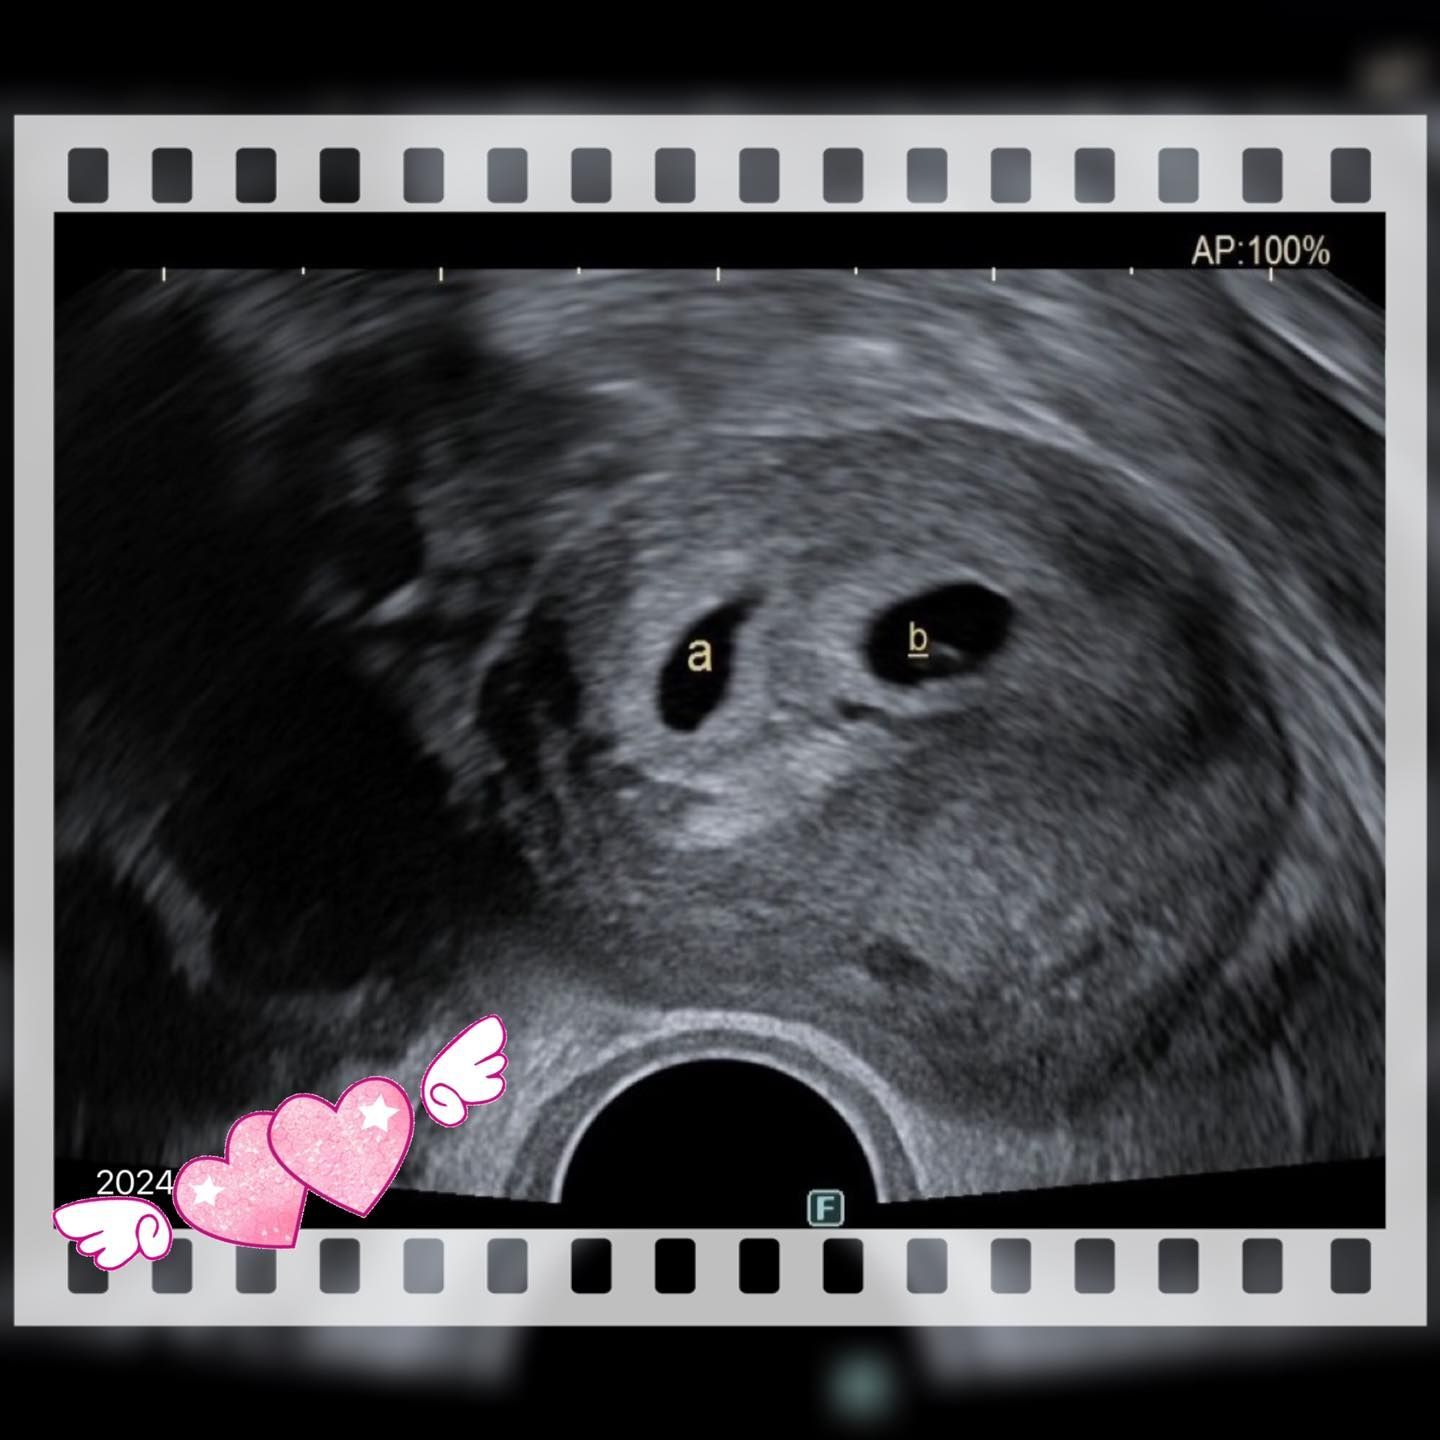

3か月間の熟慮の末、夫妻は決断を下しました。「これが最後のチャンスかもしれない」と理解しつつ、再び当センターを訪れ、卵子受贈の手続きを開始しました。センターには卵子・精子の受贈に対応する専門スタッフ(「暖卵専員」)がおり、疑問や不安を一つずつ丁寧に確認することができます。さらに自院の卵子バンクを活用することで、登録からマッチング、書類手続き、受精・移植まで、スムーズに進めることができました。心理的なハードルを乗り越えた後は、治療の流れは落ち着いて進みました。胚の培養から移植、妊娠判定、妊娠経過と、少しずつ段階を重ねることができました。

Sさんは産科検診の際に、笑顔でこう話してくれました。「年齢的に不安はありましたが、こうしてお腹の中に赤ちゃんが育っていることに心から感謝しています。」